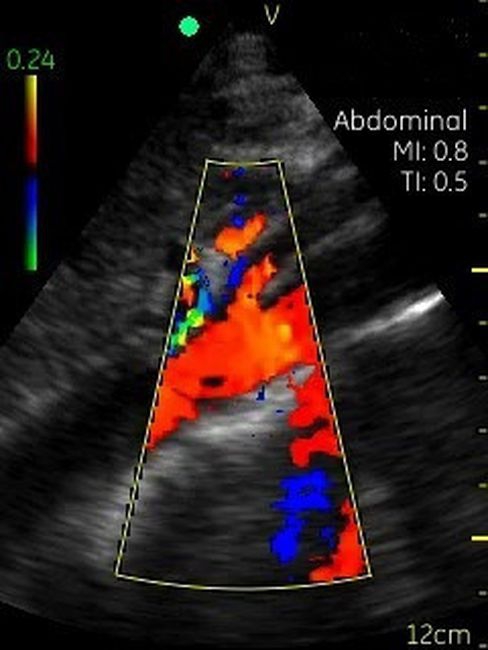

Невозможно было представить раньше, что УЗИ аппарат может помещаться на ладони руки человека. Теперь это реальность, воплощенная в корпусе и технологической начинке GE VSCAN. Инженеры заложили возможность получения дополнительной визуализации кровотока с цветной кодировкой в режиме реального времени для полноценной постановки диагноза на месте.

Визуализация Vscan:

· Черно-белый режим для визуализации анатомических структур в реальном времени.

· Наложение кровотока с цветовой кодировкой в реальном времени.

· Поле зрения в черно-белом режиме: до 75 градусов с максимальной глубиной 25 см.

· Сектор цветного режима показывает кровоток с углом обзора 30 градусов